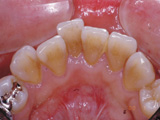

| 他院で矯正治療を受けられましたが、独断でリテーナーの使用を途中でやめてしまったため、歯並びが元に戻ってしまっている患者さんが時々来院されます。 |